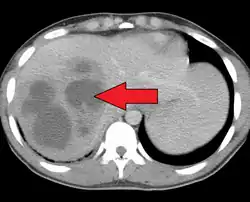

A large pyogenic liver abscess presumed to be the result of appendicitis